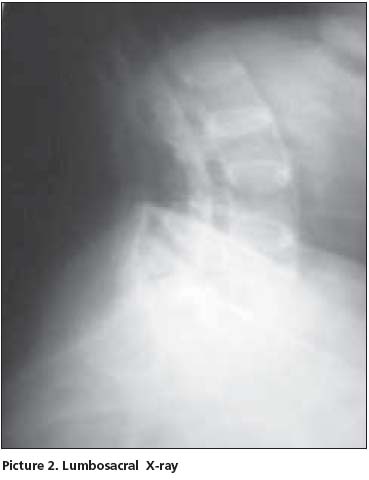

Her postero-anterior chest x-ray was evaluated as normal. In thoracic (Picture 1) and lumbosacral (Picture 2) graphs, marked squaring in her vertebras, shiny corners, symmetric syndesmophytes, bamboo spine, trolley track sign, osteoporosis and left faced scoliosis were observed. In pelvic x-ray her sacroiliac joints were normal. There were enthesopathic changes in the localization of the insertion of achilles tendon in calcaneus posterior bilaterally (picture 3). In magnetic resonance imaging (MRI) and conventional radiography, bilateral sacroiliac joints were regular and joints cartilage were normal (Picture 4,5). There were not any pathological signal changes in the bone surfaces that form the joints and the soft structures that were examined. Depending on the current clinical status and the radiography and imaging tests, the patient was defined as spondyloarthropathy (SpA).

Diagnosing axial SpA [Ankylosing Spondylitis (AS) and undifferentiated SpA(uSpA) with predominant axial involvement but without radiographic sacroiliitis] in the absence of radiographic sacroiliitis poses a major challenge to many physicians. In the absence of diagnostic criteria, classification criteria are often used to aid the diagnostic process in daily practice. The most often cited classification criteria for SpA are the Europian Spondylarthropathies Study Group (ESSG) criteria that were proposed in 1991. According to these criteria, in the absence of sacroiliitis; patients with inflammatory spinal pain or synovitis (asymmetric, predominantly in the lower limbs) in addition to any one of the following (positive family history, psoriasis, inflamatory bowel disease, alternate bottock pain, enthesopathy) are classified as seronegative SpA with 77% sensitivity and 89% specificity. In the presence of sacroiliitis, sensitivity is 86% and specificity is 87%[1]. However in a recent study from Spain, it was observed that the performance of the ESSG criteria as diagnostic criteria in daily practice was moderate: only 46.6% of patients with possible SpA who met the ESSG criteria at entry into the study were judged by their rheumatologist to have SpA after 5 years of follow up[2]. The typical radiographic changes of AS are seen primarily in the axial skeleton, especially in the sacroiliac, discovertebral, apophyseal, costovertebral, and costotransvers joints[3]. Syndesmophyits seen in AS and entheropathic arthiritis are usually symmetrical and bilateral, while that are seen in reactive arthiritis and psoriatic arthritis are nonmarginal, rough and asymmetrically located[4]. The radiological appearance of arthritic changes in sacroiliac joints has been regarded as a hallmark of AS according to Modified New York Criteria[5]. In AS patients in addition to sacroiliitis, arthritic changes in the spine visualized by x-ray develop in 57- 88% of the patients[6,7]. In literature, there were AS patients with typical clinical features but no radiological sacroiliitis[8]. Khan et al reported that radiographic sacroiliitis is frequent in AS but is not an early or obligate manifestation of the disease. In particular, relatives of AS with IBP may not show radiographic sacroiliitis even after long follow-up[9]. Rudwaleit reported that in a small proportion of AS patients may never develop radiolographic sacroiliitis despite having IBP for many years. SpA patients with predominantly axial symptoms should be considered as having a same disease entity as AS patients, independent from the presence of radiographic sacroiliitis[10]. In one study 60% of SpA patients had developed definite AS after 10 years of follow-up. It took an average of 9 years (+/-6 years) for radiological sacroiliitis to appear in these patients. A further 20% still had chronic uSpA and might have developed radiological sacroiliitis if their follow-up had been continued for a longer time[11]. Again in another family study, radiographic evidence of sacroiliitis was found in 40% of patients with a symptom duration of <10 years, 70% with symptoms for 10-19 years, and 86% with symptoms for ≥ 20 years[12]. The morphological changes used to assess spinal involvement in x-ray were syndesmophytes, shining corners, squaring, arthritis of the apophyseal joints, spondylodiscitis, bamboo spine and trolley track sign[13]. Descriptions of spinal x-ray changes typical of AS without concomitant radiological sacroiliitis are thus relatively uncommon. Besides, Moll reported that these spinal x-ray changes develop later in the course of AS and usually after radiological sacroiliitis is evident.[14]. MRI is considered to be very helpful in detecting signs of sacroiliitis that are not yet visible in x-ray[15]. Although our HLA B27 positive patient has been suffering from IBP for 10 years, no sacroiliitis was detected in her pelvic x-ray and MRI. However in her throracic and lomber x-ray, all radiological abnormalities such as squaring, shiny corner, syndesmophytes, bamboo spine, trolley track sign were clearly present. In her foot x-ray, bilateral calcaneal enthesopathy was detected.